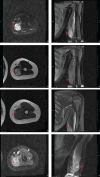

Refractory alveolar rhabdomyosarcoma in an 11-year-old male

Rhabdomyosarcoma (RMS) is a mesenchymal malignancy phenocopying muscle and is among the leading causes of death from childhood cancer. Metastatic alveolar rhabdomyosarcoma is the most aggressive subtype with an 8% 5-yr disease-free survival rate when a chromosomal fusion is present and a 29% 5-yr disease-free survival rate when negative for a fusion event. The underlying biology of PAX-fusion-negative alveolar rhabdomyosarcoma remains largely unexplored and is exceedingly rare in Li-Fraumeni syndrome patients. Here, we present the case of an 11-yr-old male with fusion-negative alveolar rhabdomyosarcoma studied at end of life with a comprehensive functional genomics characterization, resulting in identification of potential therapeutic targets for broader investigation.